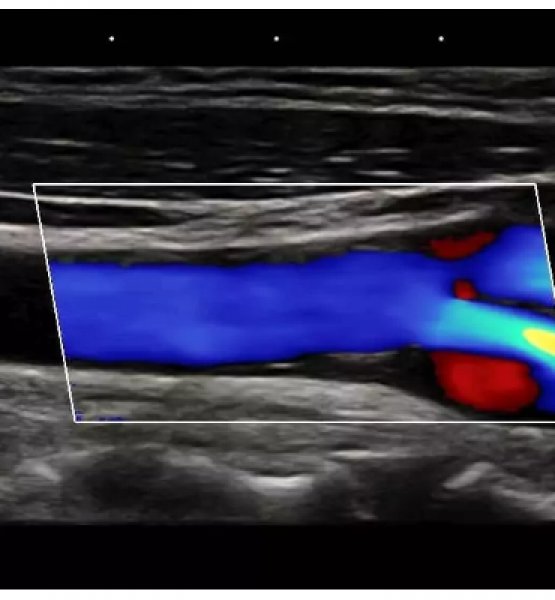

Đây là giải pháp tốt nhất cho siêu âm các cơ quan nhỏ (vú, tuyến giáp, tinh hoàn), thai nhi & thai phụ, tim (người lớn, trẻ em), Cơ – xương (thông thường & bề ngoài), mạch máu ngoại vi, thực quản, trực tràng, âm đạo & tiết niệu.